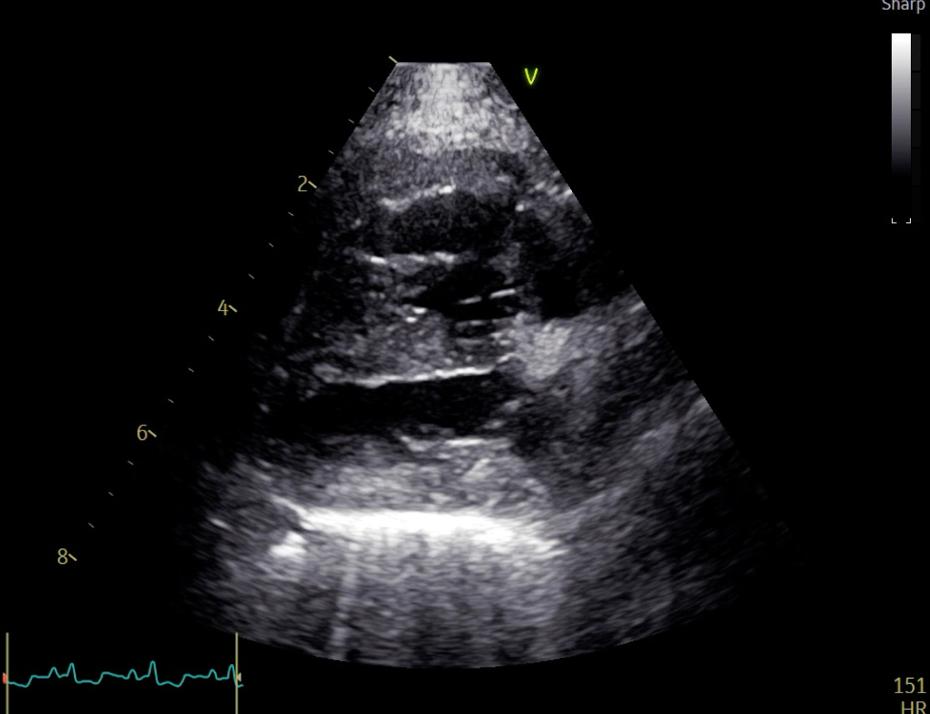

Dersom klaffelekkasjen er spesielt stor, kan hunden utvikle hjertesvikt der den får væskeansamling i lungene, lungeødem. Hunder med væske i lungene grunnet hjertesvikt vil puste tungt og raskt, ha dårligere utholdenhet og kan virke rastløse på natten. Ved mistanke om hjertesvikt tar man røntgenbilder av brysthulen eller ultralyd av lungene for å se om det er tegn til lungeødem. Hunder som har bekreftet hjertesvikt får vanndrivende medisiner i tillegg til hjertemedisinen. Hunder som har utviklet hjertesvikt med vann i lungene lever vanligvis godt i opp til et år eller to så lenge de får riktig medisiner og oppfølgning. Enkelte hunder trenger flere medisiner etter hvert som sykdommen utvikler seg og kardiologen legger en behandlingsplan etter undersøkelsen. For å kunne oppdage hjertesvikt så tidlig som mulig anbefaler vi at hundeeier teller pustefrekvens jevnlig når hunden sover: Sovende-Respirasjons-Rate–SRR. Pustefrekvens, SRR, skal være under 30 inn-pust per minutt når hunden sover. Generelt er det å telle SRR det beste verktøyet hundeeier har for å utelukke hjertesvikt hos hund med MMVD.